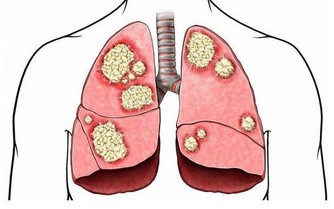

結果術後半年的一次體檢,發現她感染了艾滋病。經醫生分析,吳小姐半年前做紋眉時,感染艾滋的機率極大。工作室器具消毒不到位,很容易通過血液傳播各種疾病,其中就有艾滋病。

紋身過程不衛生,不規範,會增大感染乙肝、艾滋病、細菌性紅眼病和沙眼、梅毒、結核病等的風險。